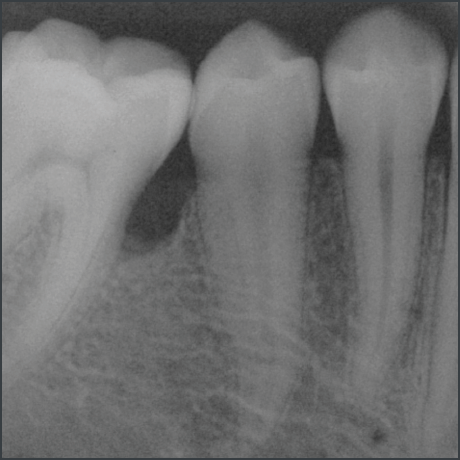

Before treatment with Straumann® Emdogain®.

Courtesy of Prof. Carlos Nemcovsky

20 years after treatment with Straumann® Emdogain®.